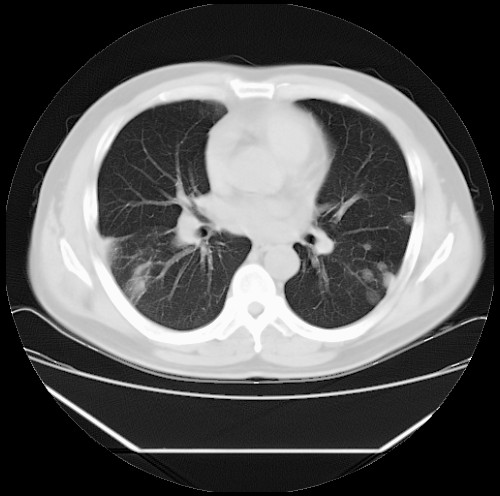

标题: CT22085:双肺多发结节

男,44岁,咳嗽,痰中带血2天。

病灶大部分位于胸膜下,结节大小相差不是很大,肺尖太干净。这种结核没见过,我认为可排除。

除肺内及胸膜下可见多发大结节外,在肺小叶中心核、小叶间隔及支气管血管束上亦可见多方小结节,可以认为是随机分布。考虑转移可能性大。

仔细观察病灶形态,病灶边界部分清楚,结合临床症状,首先考虑转移,纵隔内多个肿大淋巴结影。

双肺血管纹理末端多发类圆形结节,边界光滑清晰 气管前腔静脉后淋巴结肿大

考虑转移瘤

沿血管分布,位于血管末端。转移瘤多见,血行性菌栓也可见到。

本例双肺多发类圆形高密度灶,边清,结合病史多考虑双肺多发转移改变,可以结合实验室检查。